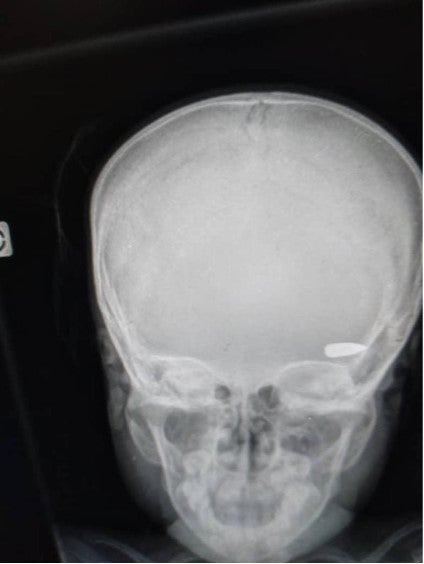

An x-ray image shows a bullet lodged in the head of a child who was hit during a confrontation between criminal groups in the Brooklyn neighborhood of Cité Soleil commune in early April 2023